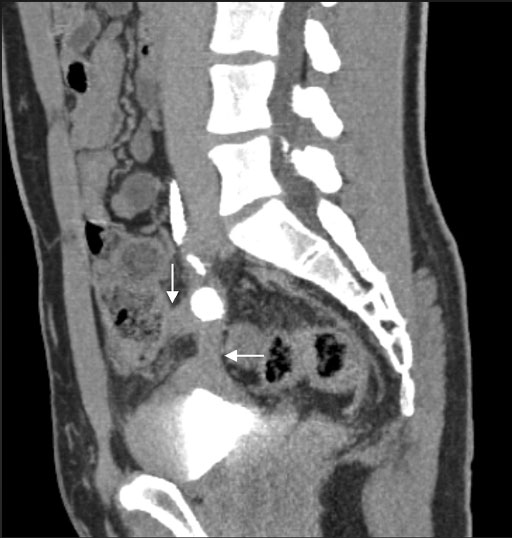

CT矢状断像で上行結腸から肥厚した膀胱頂部に連続する帯状構造物がみられ(矢印),内部に石灰化が認められる.

• 図3 造影CT矢状断像